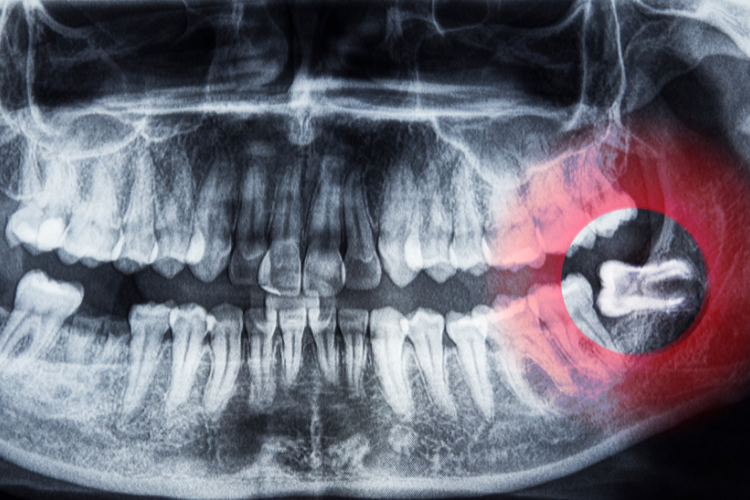

The dentist or oral surgeon will make an incision in the gum tissue to access the tooth and bone Rest and avoid strenuous activities for a day or two..

The periodontist evaluates the extent of gum disease through clinical examination, X-rays.